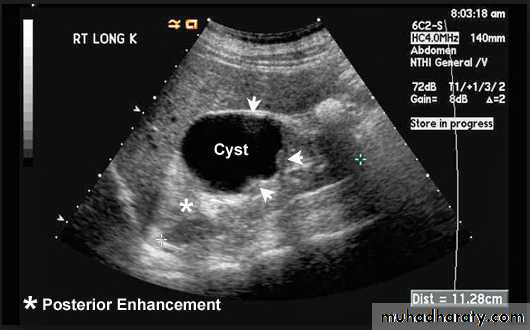

Typically, a cyst containing a clear fluid has few if any echoes (anechoic =black ) ,

Ultrasound is typically ordered to exclude , stones , hydronephrosis or to evaluate renal size or suspected renal cysts .